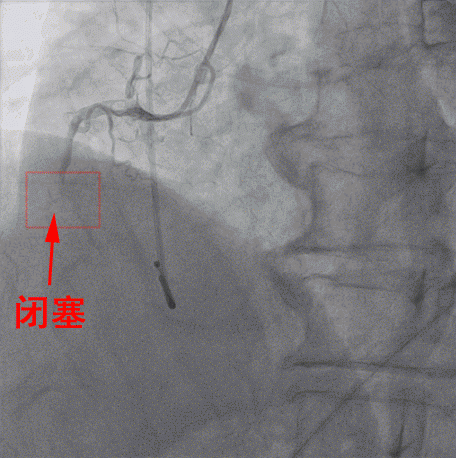

随後患者被迅速送進介入手術室,行右冠狀動脈支架手術,手術由内一科(心内)馬澤洪醫生等實施。經DSA引導下冠狀動脈造影顯示,患者右冠狀動脈近端完全閉塞,意味着右冠脈無法供血給心肌,心肌大面積處于嚴重缺血、缺氧的瀕死狀态。

專家們在DSA引導下,經右手桡動脈穿刺,置入導絲将擴球囊送至右冠脈,對閉塞處進行擴張,緊接着放置一枚支架至病變處,再用後擴球囊對支架進行擴張、塑形。DSA顯示支架貼壁良好,原先閉塞的右冠狀動脈已完全暢通,血液迅速恢複灌注,心肌重新獲得血液供養。術後患者心率維持70次/分,各項生命體征平穩,成功脫離死神。